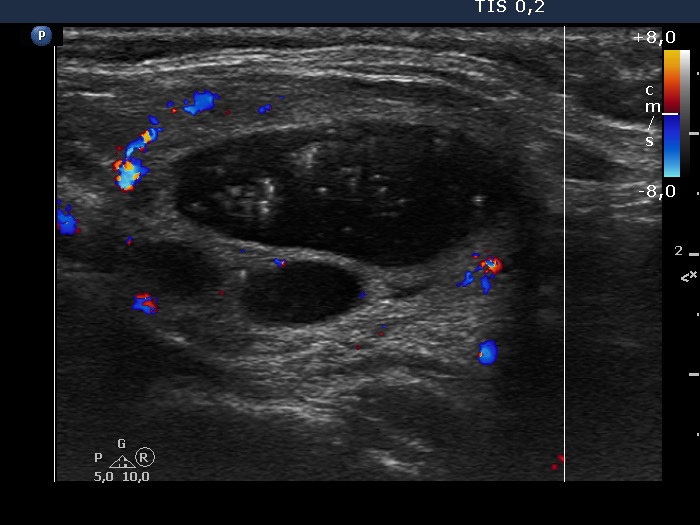

Left lobe, longitudinal scan, color Doppler mode - after aspirating of 7.5 mL brown fluid.